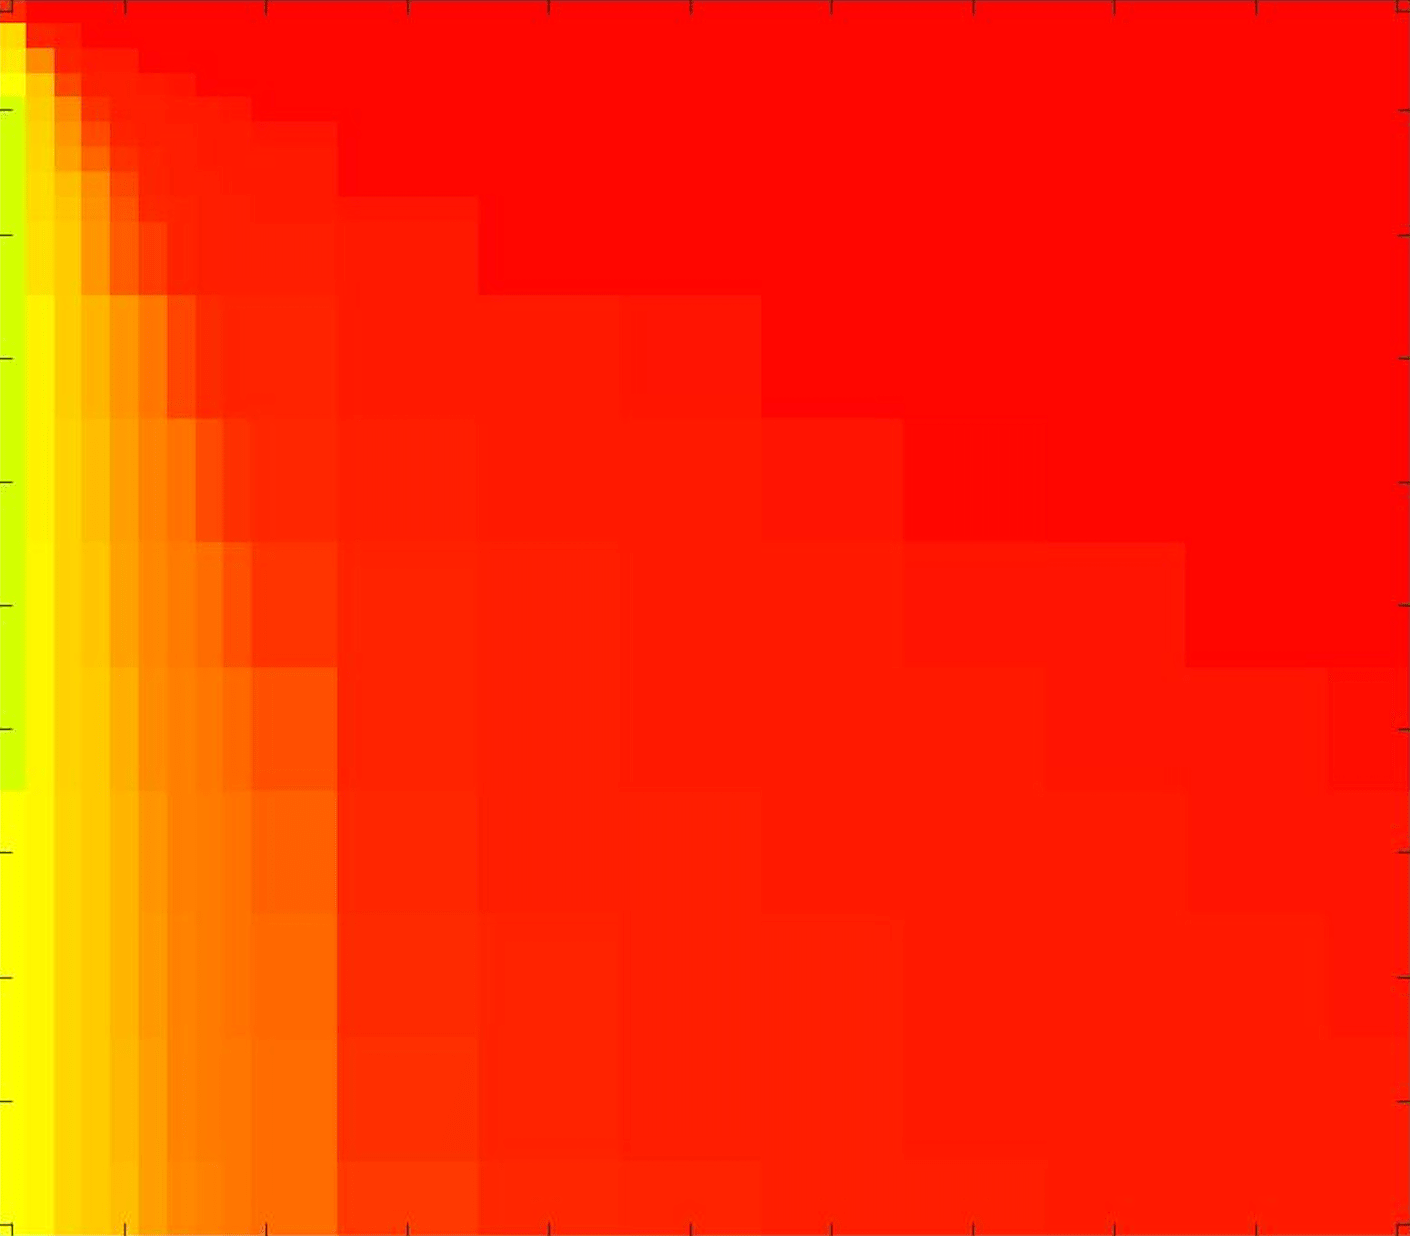

where refers to the number of points in the enclosed region. This takes values in the range , with higher TC values indicating a more accurate segmentation. In the following we will represent accuracy visually from red () to green (), with the intermediate scaling of colours used shown in Fig. 8. This will be particularly relevant in §7.2.

The TC values for the parameter sets are presented as heatmaps in Figs. 11–13. A heatmap is a convenient way to display accuracy results for hundreds of tests concisely. In Fig. 9 we give an example heatmap with the same axes used for those in Figs. 11–13. For each of the combinations of parameter values we give the TC value of the segmentation result and represent it by the appropriate colour. The corresponding colour scale is shown in Fig. 8. Qualitatively, the more green areas of the heatmap the more accurate the model is for a wider set of parameters. Example results for Test Image 5 when varying (with ) for the proposed model are given in Fig. 10. Here it can be seen what each accuracy result corresponds to visually.

Note. The axes have been removed from the heatmaps in Figs. 11–13 for presentational clarity. However, to be explicit, the axes used in all heatmaps are the same as those in Fig. 9.